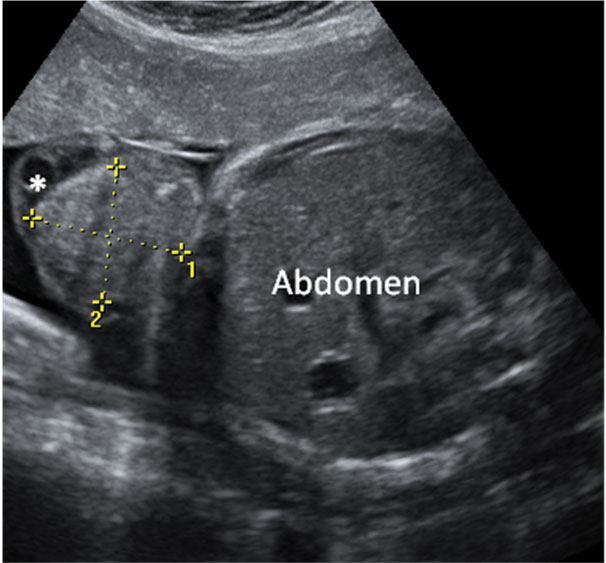

En la ecografía podemos ver una hernia intestinal (u onfalocele), lo que significa que parte del intestino del feto está fuera del abdomen. Observamos la sección transversal del abdomen fetal. A la izquierda, contenido intestinal (entre marcas de medición) herniado fuera del abdomen, debido a un defecto en la inserción del cordón umbilical, que se marca en la imagen con una estrella (*).